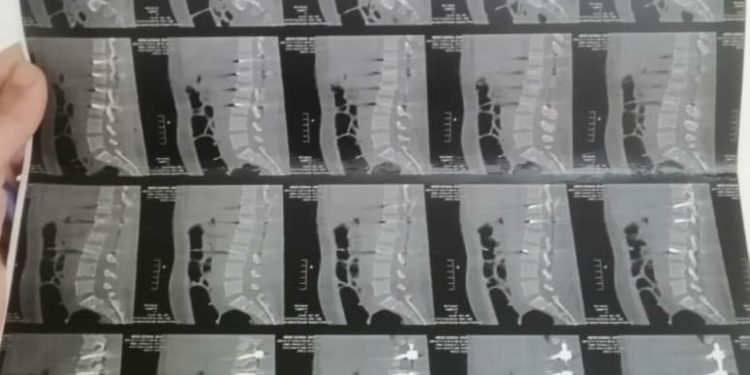

نجح فريق طبي بقسم جراحة المخ والأعصاب بمستشفى بني سويف التخصصي في إجراء جراحة دقيقة في الفقرات القطنية لمصابة تبلغ من العمر 25 عامًا، تعاني من كسر خطير بفقراتها القطنية نتيجة تعرضها لحادث سير، وذلك بحسب ما أوضحته الفحوصات والأشعة المقطعية.

وقال الدكتور أحمد صادق مدير مستشفى بني سويف التخصصي إن المصابة حضرت إلى قسم الاستقبال والطوارئ في حالة خطيرة، وبإجراء الفحوصات اللازمة لها تبين وجود كسر في الفقرات القطنية، ونظرًا لصعوبة حالتها وإمكانية حدوث مضاعفات من الممكن أن تؤثر على حركتها، جرى تجهيزها على الفور لخضوعها لعملية جراحية لتثبيت الفقرات باستخدام 7 مسامير و2 شريحة.